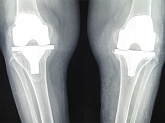

Еndoprosthesis of knee joint

In the late stages of arthrosis of the knee joint, accompanied by a pronounced restriction of the volume of movements, constant intense pain, deformity of the limb, the only way to recover is to replace the affected joint with an artificial joint - arthroplasty.

This method allows you to return the correct form of the limb, the full volume of movements in the joint, relieve the constant pain and crunch during movements and, as a result, significantly improve the patient's quality of life.

Below are presented X-ray photographs and photographs, illustrating the amount of motion in the affected joint before and after surgery.